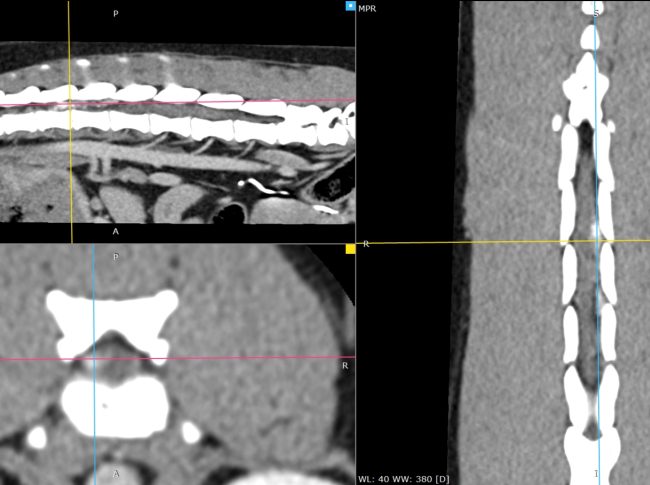

3D_MPR_-_hirault_ULA_-_12_11_2025_20_04_01_-_OS_RACHIS_1.0_0000

3D_VR_-_hirault_ula_-_14_11_2025_21_25_01_-_TISSUS_MOUS_RACHIS_1.0_0000

3D_MPR_-_hirault_ula_-_14_11_2025_21_25_01_-_TISSUS_MOUS_RACHIS_1.0_0000

Scanner cervical pré- et postopératoire – Hernie discale C3–C4 traitée par corpectomie.

À gauche : examen tomodensitométrique préopératoire montrant une hernie discale cervicale C3–C4 nettement latéralisée à droite, responsable d’une compression médullaire.

Au centre : scanner de contrôle postopératoire immédiat avec reconstruction 3D, mettant en évidence une corpectomie C3–C4 parfaitement centrée sur l’espace intervertébral, conforme à la planification chirurgicale.

À droite : reconstruction multiplanaire postopératoire confirmant que la fenêtre de corpectomie permet une décompression complète de la moelle épinière, y compris sur la composante latéralisée de la hernie.